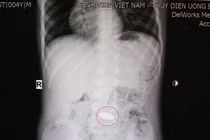

Các bác sĩ tại Bệnh viện Nhân dân Gia Định vừa thực hiện thành công ca nội soi, gắp dị vật vỏ thuốc cho người bệnh D.H.L, 18 tuổi, ngụ tại quận Bình Thạnh, TP HCM. Người bệnh cần thận trọng khi uống thuốc để tránh nhập viện cấp cứu.